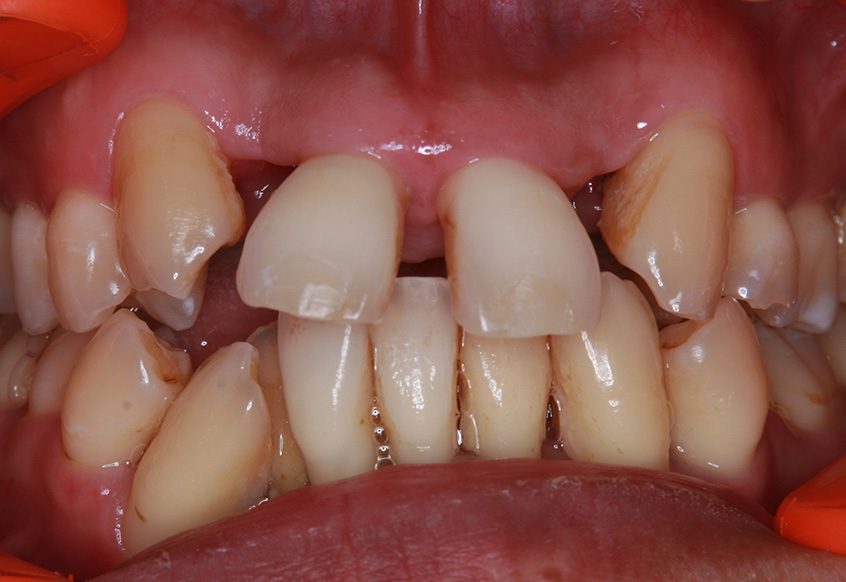

親知らずの痛みがなくなった患者さんは、昔から歯並びが気になっていることを打ち明けてくれました。特に上の歯が少し前に出ていたり、隙間があったりしている点を治したいそうです。そこで、まず上の歯並びの矯正治療を開始しました。

最初のお口の中 ワイヤー装着して治療を開始

治療開始後3ヵ月経過すると、前歯の隙間や全体の乱れが減ってきました。口笛が吹けるようになったとのことです。

最初のお口の中 治療開始3ヵ月後